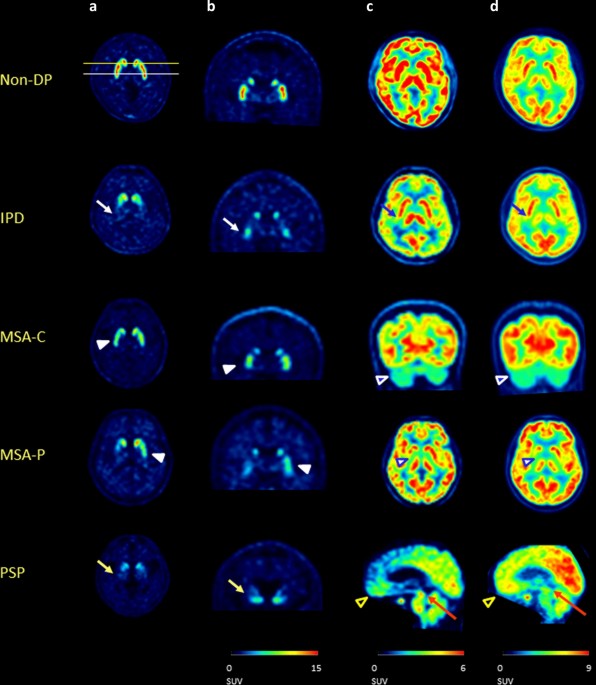

Diagnostic Accuracy Of Dual Phase 18f Fp Cit Pet Imaging For Detection And Differential Diagnosis Of Parkinsonism Scientific Reports